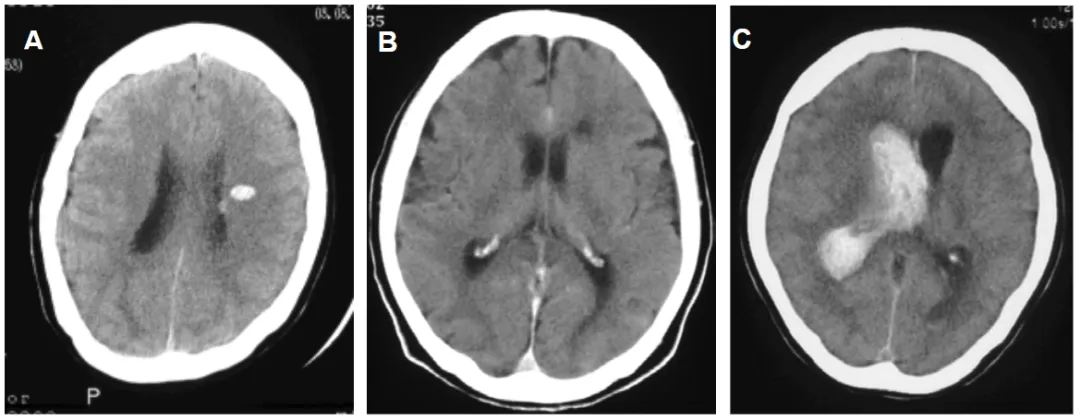

后部出血的代表性 CT 图像

A:顶叶及枕叶出血 | B:原发性脑室内出血(后部分布型)C:侧脑室后部室管膜下区出血(箭头所示)

A:丘脑出血 | B:颞叶后半部出血 | C:胼胝体后半部出血